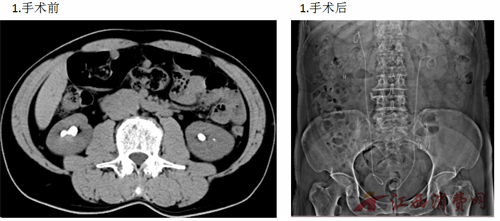

2026年新年伊始,上饶市立医院泌尿外科团队传来捷报——连续成功为三例双侧肾输尿管结石患者实施输尿管软镜钬激光碎石术,所有病例均实现一次性完整粉碎结石,即刻清石率达到极高水平,患者术后恢复顺利,彰显了上饶市立医院在复杂泌尿系结石微创诊疗领域的过硬实力。